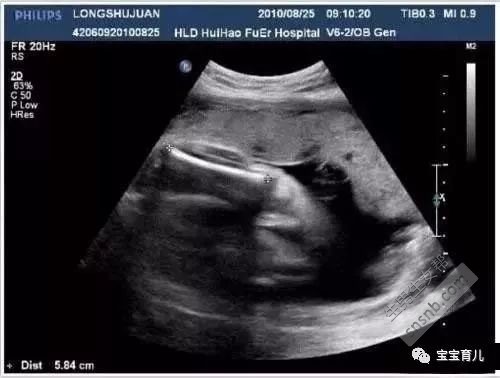

1、7W+1D的B超数据:胎囊2.9*1.9,生的是男孩儿。

2、60天的B超数据:孕囊大小是3.6*1.6mm,生的是男孩儿。

3、5W+6D,孕囊25*11mm,男孩儿。

4、62天,孕囊2.6*1.8,可爱的男孩儿。

5、孕囊长44*20mm,生的也是男孩儿。

总结:初期B超哦胎囊是长条形的,怀男孩的几率就会大一些~